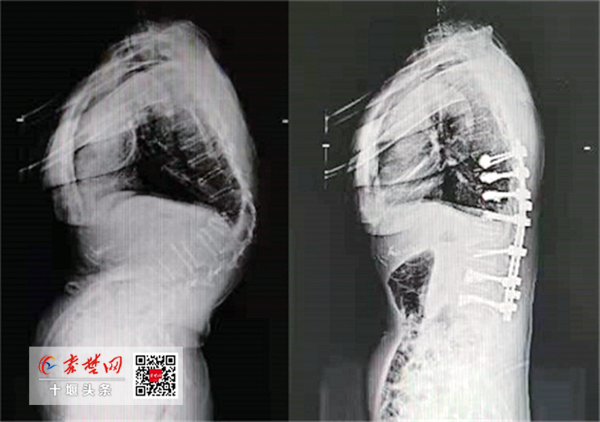

王达义为刘女士完善了相关检查,发现她是陈旧性胸腰椎骨折因没有得到及时正确的处置,导致后凸畸形后遗症发生。她的驼背明显,脊柱后凸达到70度。同时,驼背畸形导致腰背部肌肉韧带长时间受到牵拉紧张损伤,引起慢性腰背痛。

经过充分的手术评估及术前准备,刘女士及家属同意手术方案。很快,王达义带领团队为她开展手术治疗。“术中,我们要剥离包绕的神经、血管,并将其保护起来,然后将其中一个椎体切掉一半,再通过10个螺钉固定。”王达义说,截骨较为顺利,但在打螺钉时,由于患者有严重的骨质疏松,导致螺钉打不牢,于是通过注入俗称“骨水泥”的医用胶水,使螺钉紧固。

术后,刘女士后凸的脊柱得到彻底纠正,身高增加8厘米。医生介绍,困扰刘女士多年的腰背疼痛也将随着术后康复慢慢消失。

编后:医疗技术是医疗质量的内在核心,是不断提升医疗服务能力,满足人们医疗服务需求的必由之路。“十三五”以来,在市委市政府的领导下,在市卫健委的指导下,太和医院奋楫笃行,在前沿医疗技术的开展和运用上取得骄人成绩。一项项前沿技术、核心技术、特色技术频繁开展,实现外科手术微创化、内科治疗外科化、介入治疗常态化,尤其在心脑血管疾病、恶性肿瘤等慢性疾病、微创外科、介入治疗等救治领域取得重大进展,一大批国家、省级诊疗中心相继落户太和医院,为区域百姓筑起强有力的健康屏障。术前术后影像对比